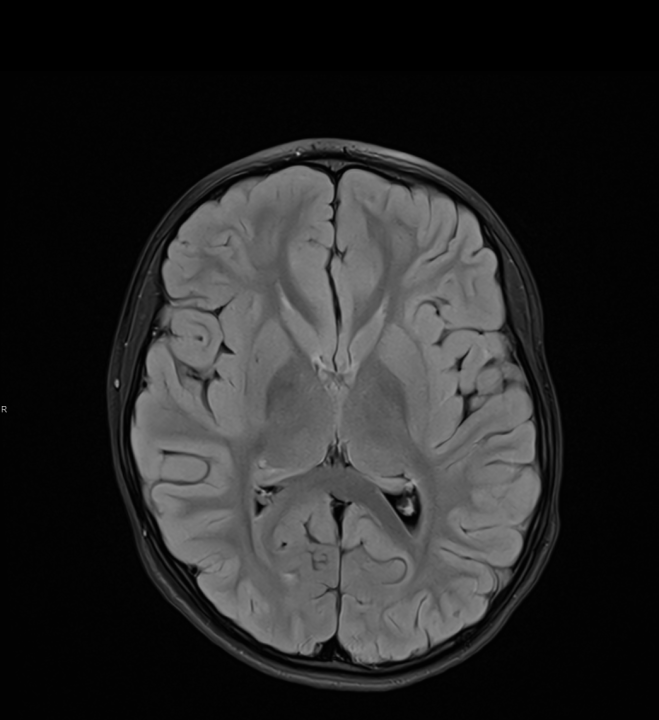

Tijekom Tjedna mozga Poliklinika Affidea Vita daje 20 posto popusta na magnetsku rezonancu!

Povodom obilježavanja Tjedna mozga od 11.

MR mozga

MR angiografija